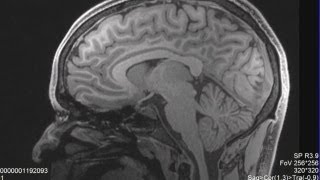

Concussion program to scan Lobos' brains

Anxiety/Mood Trajectory of Concussion | UPMC Sports Medicine Concussion Program MRI Won't Show Concussions

MRI Won't Show Concussions 90% of Brain Scans Miss Concussions After a Wreck